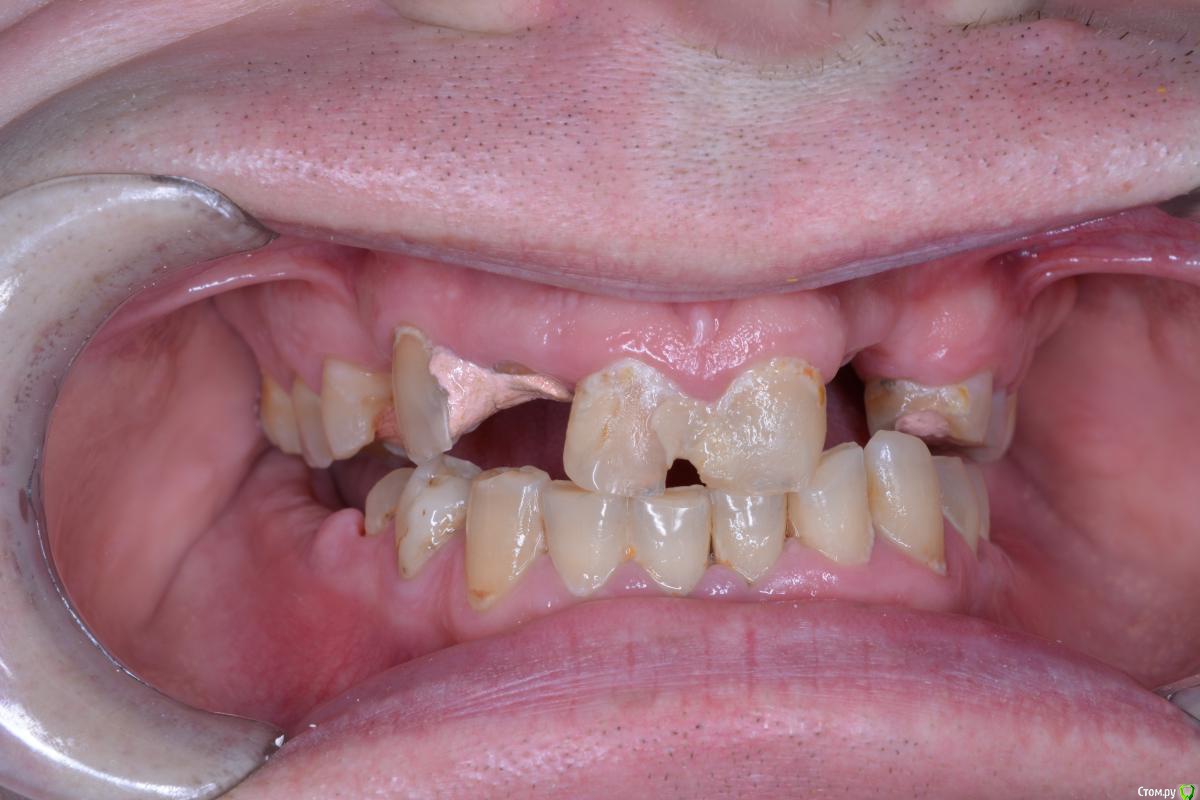

alekcandr ovs. Опубликовано 9 января, 2018 Поделиться Опубликовано 9 января, 2018 Пациент 43 года, очень боялся стоматологов и доболтаться до такого, с чего начать ???Мой предварительный план лечения депрограмация ,регистрация Ц.С, поднятие прикуса , Wax up ,хир.удлинение 1.1,1.6,1.7,2.1,2.4,2.5,2.6,2.7,имплантация 3,4 сегмент, тотал В.Ч, Н.Ч мостовидные протезы 1.5--1.3----1.1 2.1-------2.4,2.5.может искус.десна фронт !!!! 1. Вопрос чем лучше депрограмировать и найти Ц.С ????2.На сколь максимум можно удлинять моляры В.Ч ограничитель трифуркация ??? 3. Коллеги помогите сложный для меня случай!!! Всем добра Ссылка на комментарий